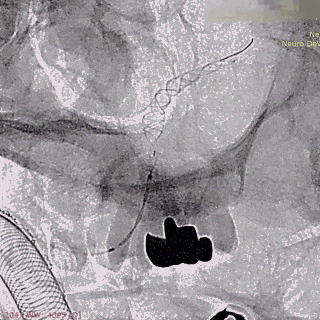

第二枚支架远端释放。

第二枚支架释放至中段。

中段释放适当推挤系统,保持贴壁良好。

中段释放后造影。

继续释放支架。

继续释放支架,造影观察贴壁良好。

完全释放支架。

支架微导管沿推送导丝上高并将推送导丝撤出。

术后即刻造影。

术后重建。